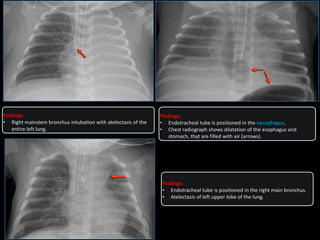

• Right mainstem bronchus intubation with atelectasis of the

entire left lung.

Findings:

• Endotracheal tube is positioned in the right main bronchus.

• Atelectasis of left upper lobe of the lung.

• Endotracheal tube is positioned in the oesophagus.

• Chest radiograph shows dilatation of the esophagus and

stomach, that are filled with air (arrows).